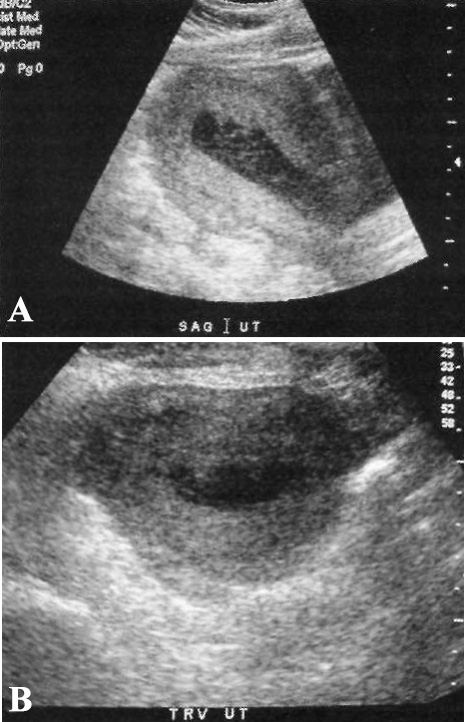

УЗИ при эндометрите не имеет характерной ультразвуковой картины. Ультразвуковое исследование может выявлять утолщение эндометрия, воздух и жидкость в маточном канале, однако – это неспецифические признаки в послеродовом периоде (фото 1).

Фото 1. Эндометрит. Ультразвуковое исследование в сагиттальной и поперечной плоскостях. Пациентка предъявляет жалобы на боли и повышение температуры тела, которые продолжаются в течение 10 дней после кесарева сечения. Визуализируется неоднородная жидкость в полости матки и неравномерный толстый эндометрий (такая картина не является специфичной для эндометрита)